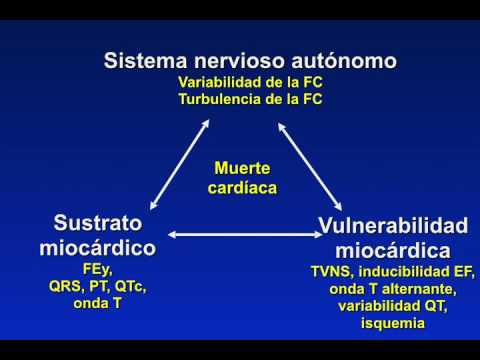

CDI y TRC en prevención de Muerte Súbita – Wojciech Zareba

Muerte súbita en mujeres. Dra. María Eugenia Döppler. Residencia de Cardiología. Hospital C. Argerich. Buenos Aires